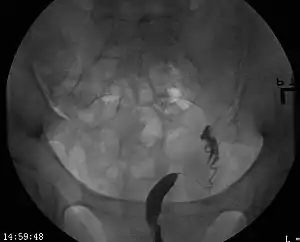

| A unicornuate uterus as seen on a hysterosalpingogram | |

Helpful techniques to investigate the uterine structure are transvaginal ultrasonography and sonohysterography, hysterosalpingography, MRI, and hysteroscopy. More recently 3-D ultrasonography has been advocated as an excellent non-invasive method to evaluate uterine malformations.[4]